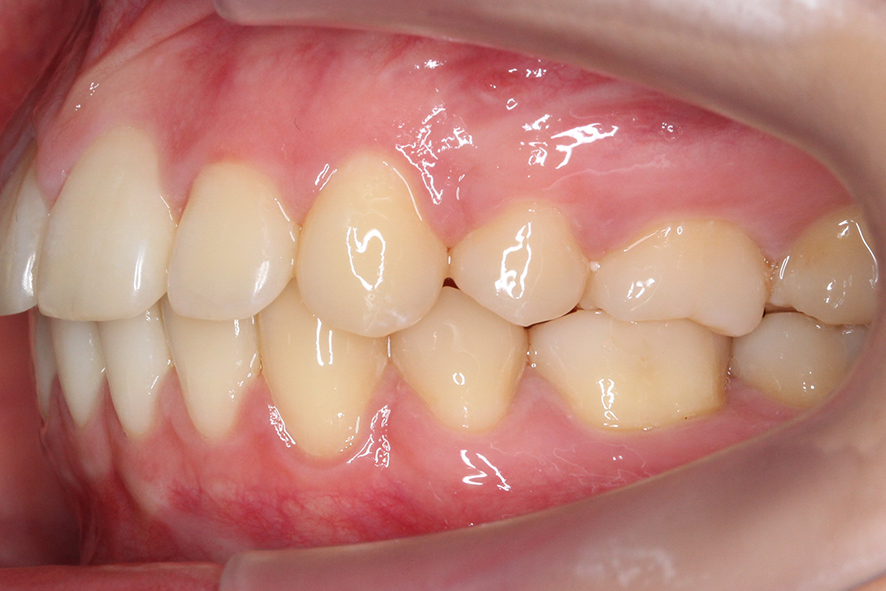

overjet 사진을 보면 돌출감이 심해 보이지

않았던 정면 및 overbite 사진과 달리

상악의 뻐드러짐이 심한 모습인데요,

구치부 교합을 확인해봐야 알겠지만

상악이 과하게 발달한 2급 부정교합

증상이 있을 것으로 보입니다.

치아의 교합평면을 보면 구치부의

교합 상태가 정상적인 치아교합과

다른 모습을 확인할 수 있는데요,

상악이 하악보다 앞쪽으로 나와 있어

어금니의 상하악 교합이 어긋난 모습입니다.

반대쪽 교합 평면 또한 상악 악궁의 길이가 길고

과도하게 발달하였기 때문에 어금니의

위치가 앞쪽으로 밀려나듯이 교합되는 모습입니다.